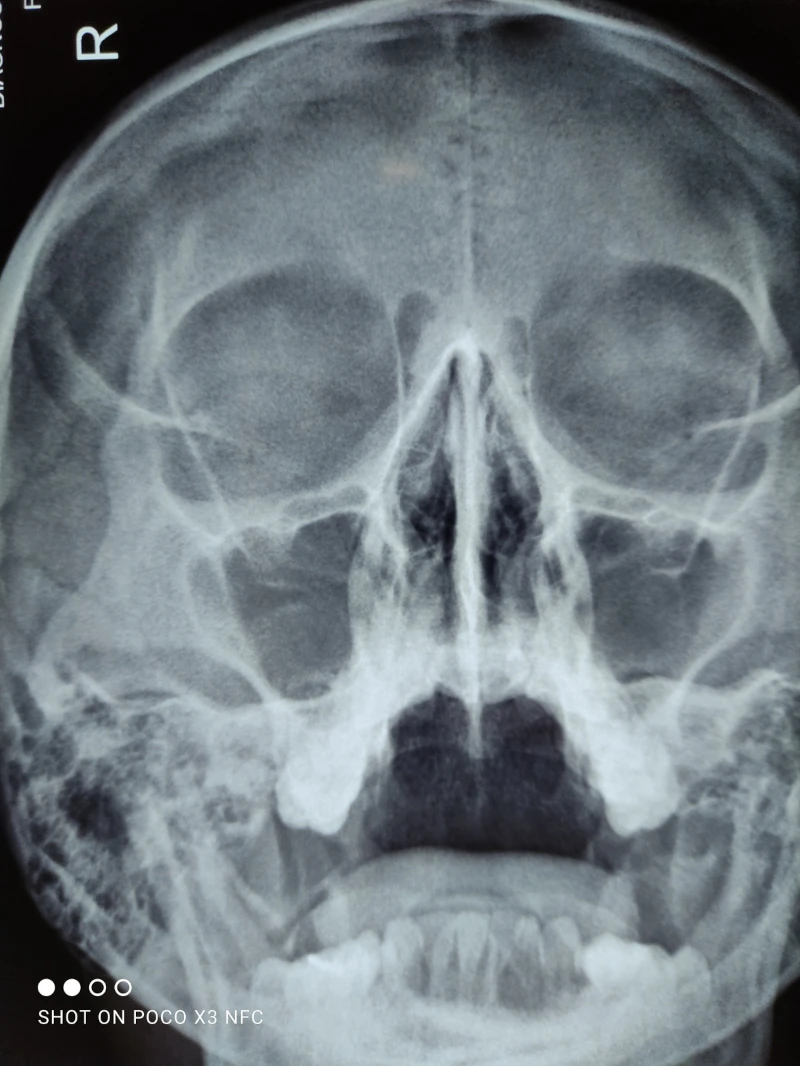

04. Sinusitis (infección de los senos paranasales)

06. Fractura nasal

08. Deformidad del tabique

03. Polipo nasal